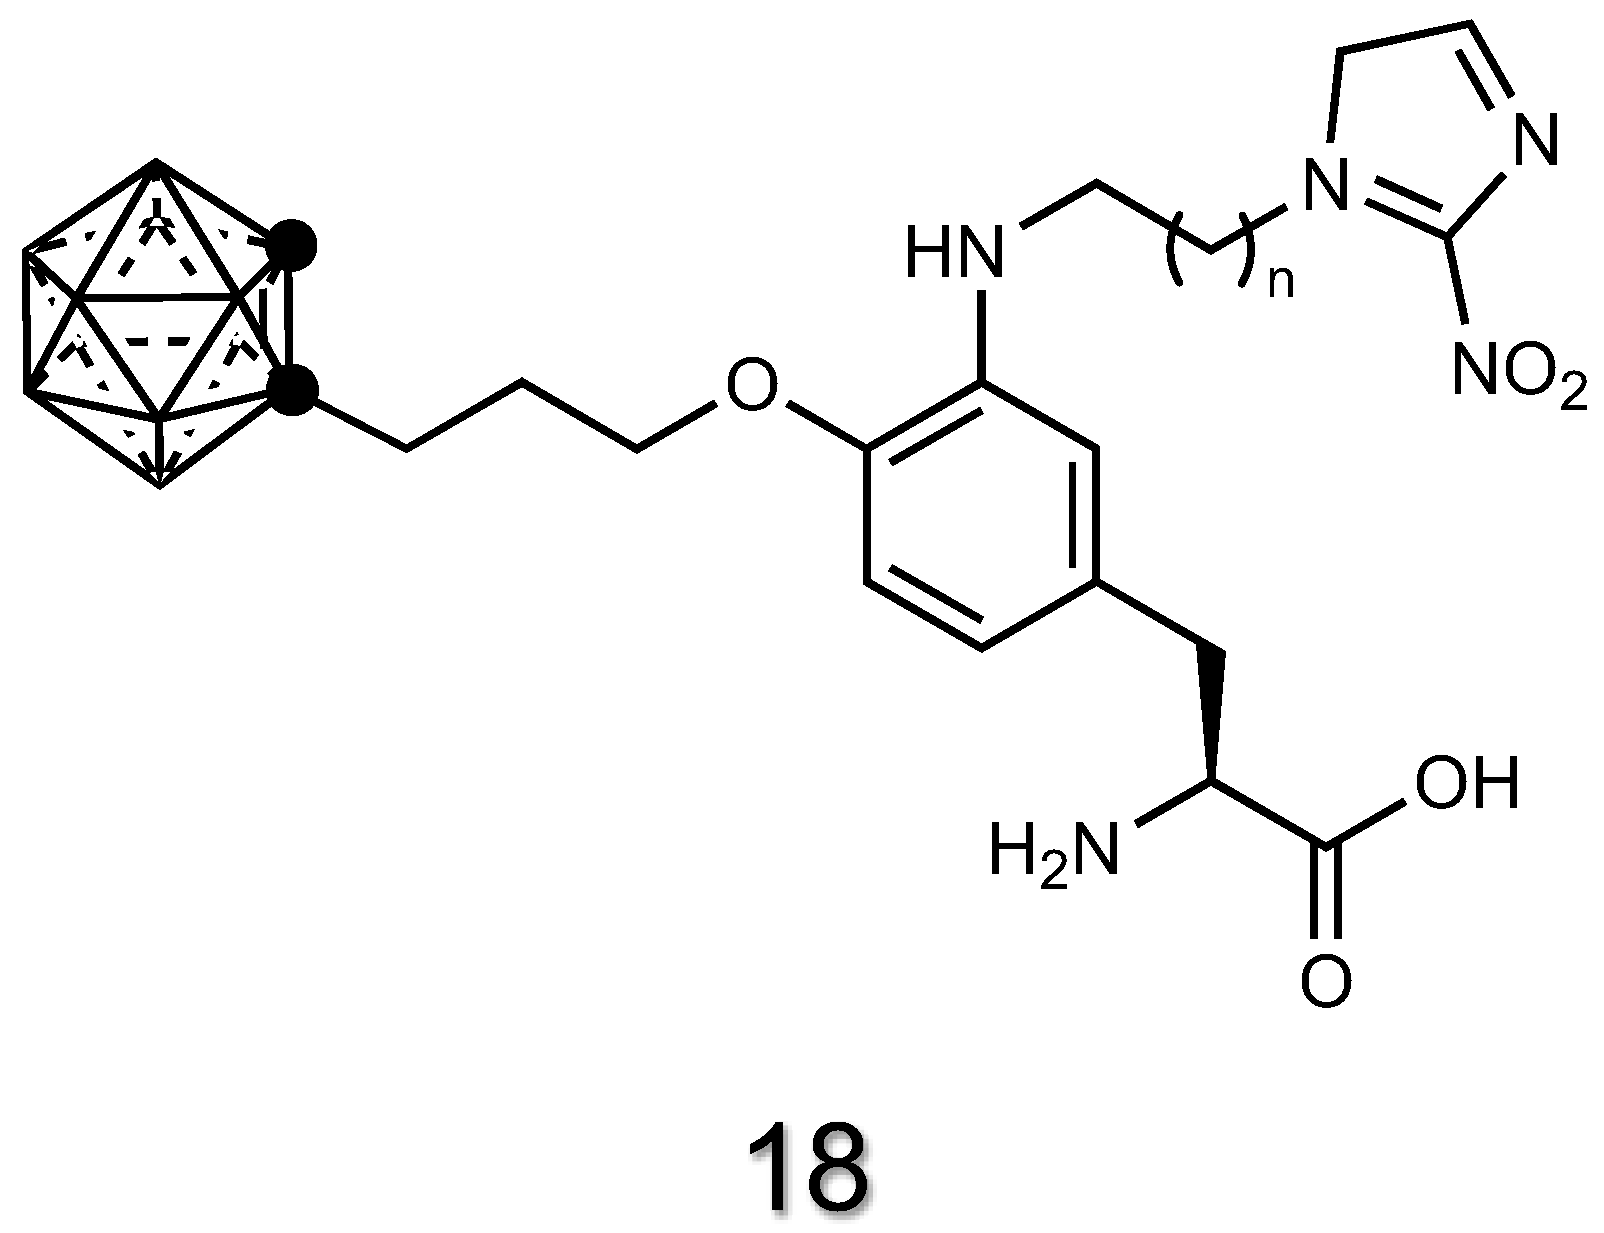

2.1.6. Amino Acid Derivatives of Carboranes